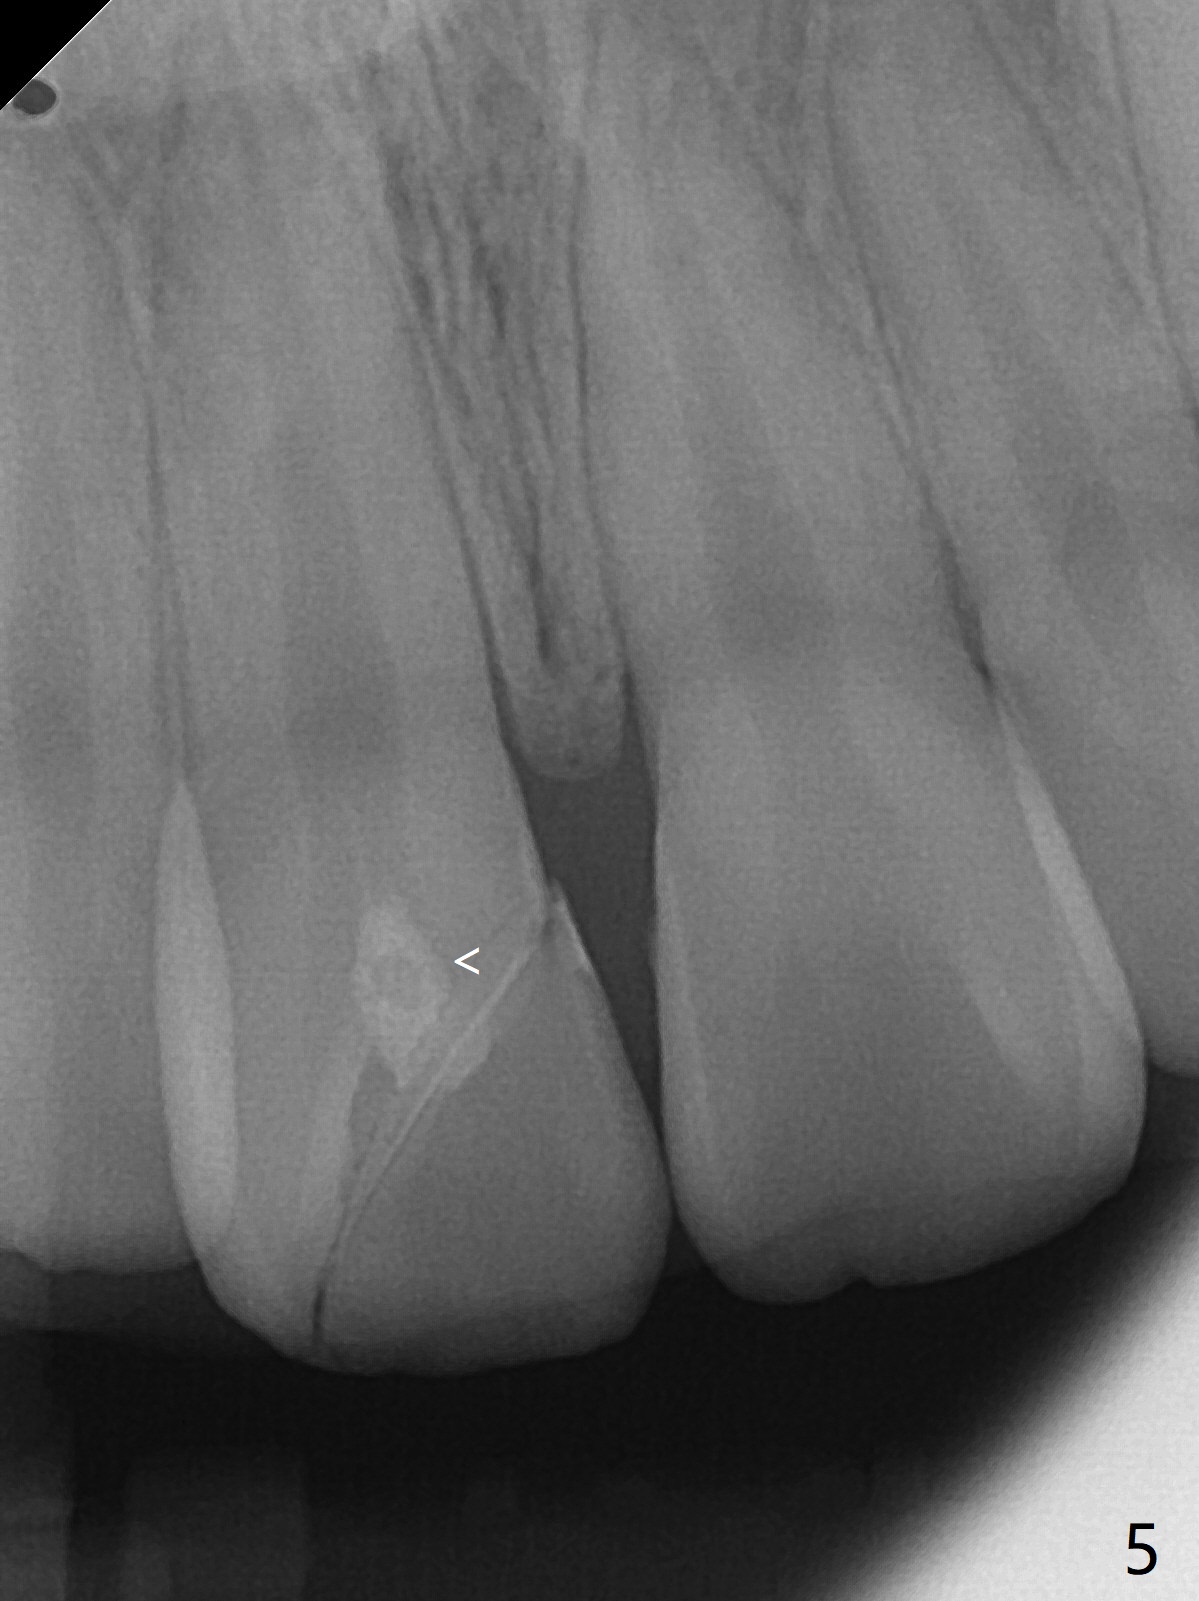

A 16-year-old man fractured the tooth #8 yesterday (Fig.1) with pulpal exposure (Fig.2) and slightly subgingival (Fig.3 <). With 2 gingival retraction cords, rubber dam and floss, the mesial margin is exposed (Fig.4). The mesial pulpal horn is increased slightly with a 330 bur with minimal pulpotomy. MTA is applied (Fig.5 <). A curette is placed over the MTA for hemostasis while it is setting. RelyX Ultimate Adhesive Resin Cement bonding is used to reattach the fracture fragment in place (Fig.6,7). Pulpal vitality will be monitored. A crown will be placed if the tooth discolors due to MTA and the pulp remains vital. Mineral trioxide aggregate (MTA), composed mainly of tricalcic silicate, tricalcic alluminate, bismuth oxide, is a particular endodontic cement. It is made of hydrophilic fine particles that harden in the presence of dampness or blood. The re-attached tooth remains asymptomatic 9 days postop (Fig.8) when he returns for prophy.

16岁男孩,昨天右上中切牙撞击电脑发生折裂(图一),近中牙髓角暴露(图二),裂缘稍微龈下(图三 <),使用两个牙龈牵拉线,橡皮障和牙线,近中折裂边缘暴露(图四)。你会如何处理?使用330钻头稍微扩大髓角开口,去除少量牙髓,填入微量MTA (图五<),希望形成新的牙本质,关闭开口,维持牙髓活性。出血控制后,应用树脂粘合剂将断片固定于原位(图五,六,七)。术后9天牙齿无症状(图八),病人回来洗牙。